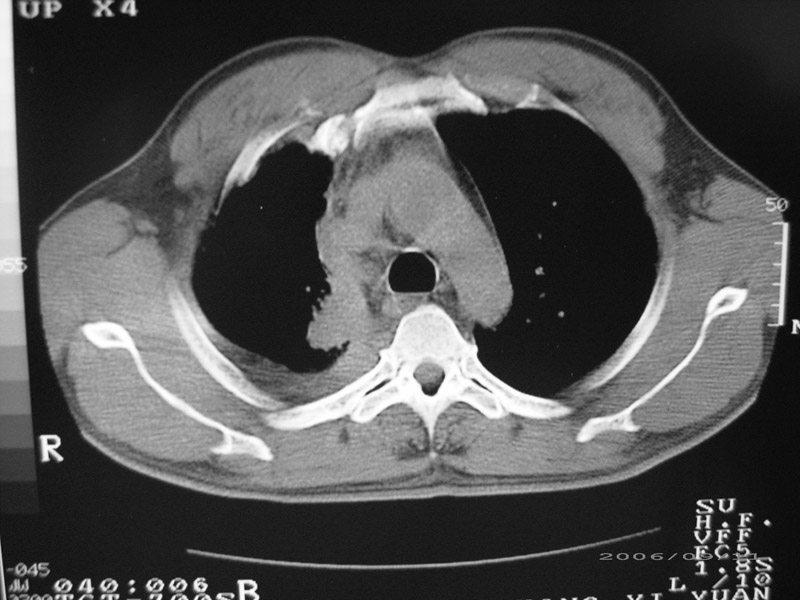

以下是引用守望可可西里在2006-9-11 15:29:00的发言:[br][br] ct平扫表现:右侧胸膜腔缩小,积液,胸膜增厚且不均匀、不规则,以纵隔胸膜增厚为主,边缘呈锯齿状,并见附壁内突之结节状肿块影。右肺含气量减少,纹理聚集,右肺门中下部见数个肿大的淋巴结。纵隔无移位,内未见明显肿大淋巴结,双侧主支气管以及各叶、段支气管比较通畅。。[br] 考虑:右侧胸膜恶性间皮瘤,伴肺门淋巴结转移。